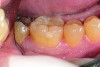

Fig 4 and Fig 5. Occlusal (Fig 4) and buccal (Fig 5) 42-month recall views of the Class I and Class V GIC restorations placed with bulk-fill EQUIA technique.